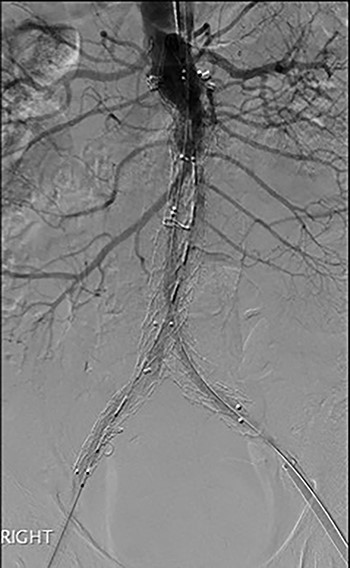

3D reconstruction CT scan, at 6-week interval from index procedure.

The patient was transferred to the high-dependency unit for observation during the thrombolysis. After 4-h, the patient was taken back to Interventional Radiology department for a check angiogram (Fig. 3). This demonstrated a fully re-canalized aorto-iliac system with no distal thrombotic or embolic complications. The thrombolysis infusion was stopped at this stage. In the post-operative period, anticoagulation has been continued with Apixaban. A CT scan 6 weeks post-procedure has confirmed ongoing patency of the endograft with no visible thrombus (Fig. 4).